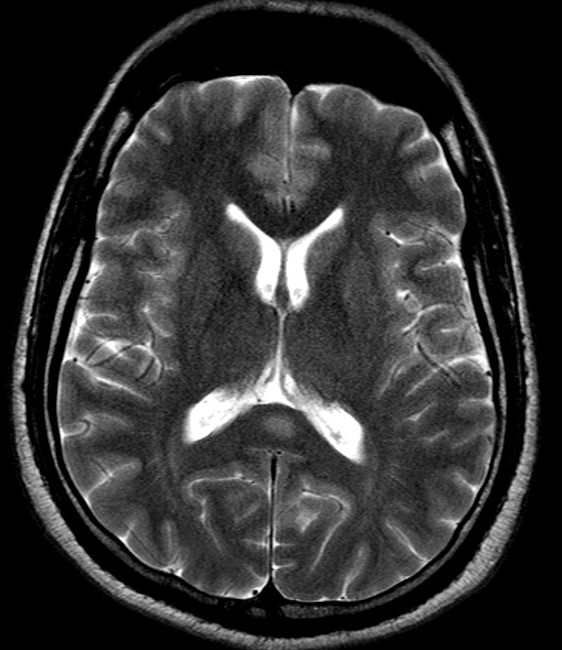

Демиелинизирующие заболевания мозга: МРТ изображения